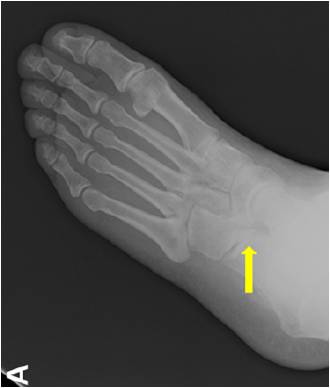

放射学检查:拍摄足负重正侧位 ,45°内斜位,跟骨轴位X线片。

放射学特征:跟距联合在侧位X线片上呈现C sign,跟舟联合在侧位X线片上呈现食蚁兽鼻征 拍摄45°内斜位X片观察跟舟联合。跟骨轴位(Harris and beath): 跟骨轴位X线片观察跟距联合。